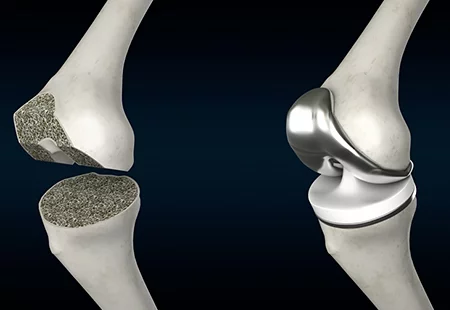

Knee arthroplasty, commonly called knee replacement surgery, replaces the damaged parts of the knee joint with high-quality artificial implants. It is ideal for patients suffering from severe arthritis, cartilage loss, deformity, chronic knee stiffness, or injury-related degeneration. This procedure helps restore smooth movement, reduce pain, correct alignment, and improve your overall quality of life.